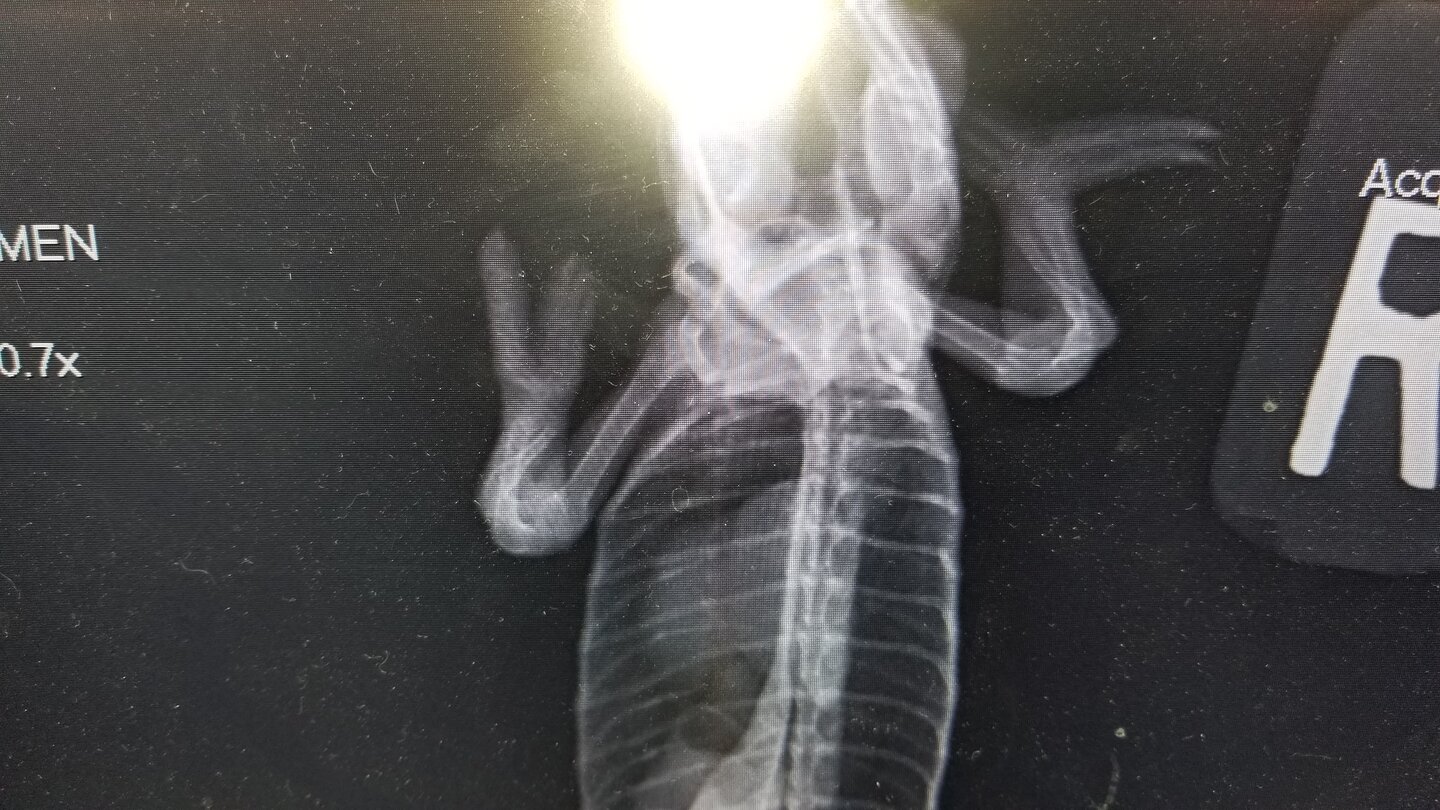

This is his latest Xray.

The vet says his bones are now 85% normal density.

But the leg bones will never straighten. And the fact that he has long suffered from MBD is proven